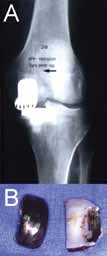

Fig. 2 Wrong component sizing or positioning may lead to edge loading (A) resulting in increased wear and implant failure (B). |

While UKA may have advantages as a surgical option for selected patients who meet the operative criteria detailed previously, TKA remains a popular operation for unicompartmental pathology. The widespread performance of UKA has been limited by the technical difficulty of performing the procedure. In particular, UKA has less tolerance for acceptable component positioning when compared to TKA, as improper component positioning, by as little as 2°, can result in UKA failure (Figure 2).[5,37,46,62-68] Failures of UKA occur when there is medial-lateral mismatch, inadequate stability of the components, heterogeneous polyethylene wear, improper patient selection (such as performing UKA for bilateral osteoarthritis), aseptic loosening, and tibial subsidence (Figure 3A and 3B).[4,27]

| Fig. 3 Disease progression of the other compartment from overstuffing, over-correction or misbalance (A), early loosening (B) and wrong component positioning may lead UKA failure. |

Improper alignment is considered to be the leading cause of UKA failure (Figure 3C).[28,61]

Maligned components often lead to impaired joint biomechanics, and eventual knee pain.[5,69,70] Reports in the literature have associated a technically poor UKA operation with accelerated polyethylene wear, an accelerated progression of the pathology to the contralateral compartment, and, in some rare instances, femoral fracture.[5,28,63,71,72,73] Strict adherence to operative technique and acceptable tolerances are required to maximize the benefits of UKA. Preservation of adequate bone stock is crucial to surgical success, leading to a shorter recovery and rehabilitation time.[25,28,45] Further, excessive bone resection often results in poor tibial component stability, which has been associated with a more difficult conversion to TKA if revision arthroplasty is eventually required.[4,68] The technical demands of performing UKA, coupled with the small margin for error, have limited the widespread adoption of this surgical intervention for unicompartmental knee pathology and many surgeons and patients remain wary of the historically inconsistent post-surgical results published in the literature.